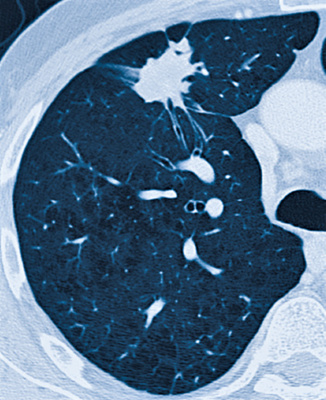

«Tree in bud» – Feinknotige entzündliche Verdichtung von ganz peripheren kleinsten Luftwegen, die sich aufzweigen und einem Zweig mit Blüten ähneln.

Hochauflösende Computertomographie HR-CT

Die hochauflösende Computertomographie (HR-CT) der Lunge spielt eine wichtige Rolle in der Abklärung von Erkrankungen, welche die feinen Strukturen der Lunge betreffen.

Aufgrund der hohen Auflösung – High-Resolution – können Erkrankungen der luftleitenden Wege und der Lungenbläschen entdeckt und anhand spezifischer Veränderungen bestimmten Erkrankungen zugeordnet werden. Die Basiskriterien dieser Veränderungen stellen netzförmige und knötchenförmige Verschattungen sowie eine vermehrte oder verminderte Dichte der Lunge dar.

Lungenerkrankungen können dabei mit der HR-CT schon erkannt werden, wenn das Lungenröntgenbild noch unauffällig ist. Die HR-CT ist aus dem diagnostischen Prozess neben Labor, Lungenfunktion, Bronchoskopie und als Ergänzung des Thoraxröntgens nicht mehr wegzudenken.